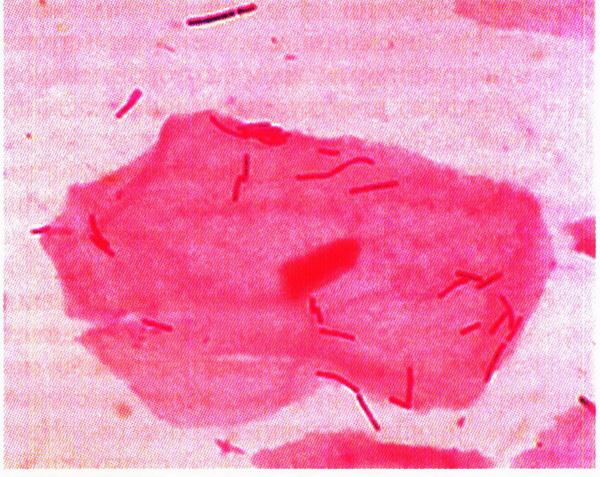

В норме влагалищная микрофлора весьма разнообразна. Она представлена грамположительными и грамотрицательными аэробами, факультативно– и облигатно–анаэробными микроорганизмами. Большая роль в микробиоценозе принадлежит лакто– и бифидобактериям (палочкам Дедерлейна), которые создают естественный барьер для патогенной инфекции (рис. 12.1). Они составляют 90–95% микрофлоры влагалища в репродуктивном периоде. Расщепляя гликоген, содержащийся в поверхностных клетках влагалищного эпителия, до молочной кислоты, лактобактерии создают кислую среду (pH 3,8–4,5), губительную для многих микроорганизмов. Количество лактобактерий и соответственно образование молочной кислоты уменьшаются при снижении уровня эстрогенов в организме (у девочек в нейтральном периоде, постменопаузе). Гибель лактобацилл наступает в результате использования антибиотиков, спринцевания влагалища растворами антисептических и антибактериальных препаратов. К влагалищным палочковидным бактериям относятся также актиномицеты, коринебактерии, бактероиды, фузобактерии.

Рис. 12.1. Микроскопия влагалищного мазка. Влагалищный эпителиоцит на фоне лактобактерий